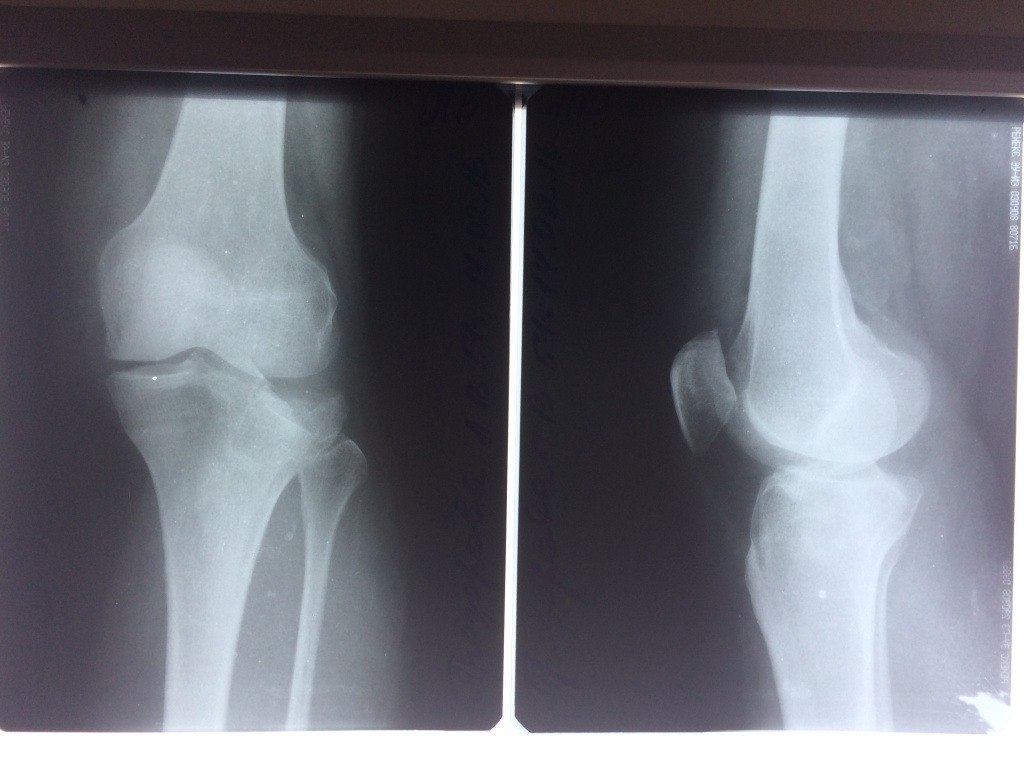

Использование материала Остеоматрикс при импрессионном оскольчатом переломе наружного мыщелка большеберцовой кости по типу Schatzker II

Использование материала Остеоматрикс при импрессионном оскольчатом переломе наружного мыщелка большеберцовой кости по типу Schatzker II.

Операция - открытая репозиция, остеосинтез большеберцовой кости опорной пластиной с костной ксенопластикой маетриалом "Остеоматрикс". На контрольных снимках в три и шесть месяцев имеется консолидация перелома, миграции фиксатора нет, имеется остеоинтеграция ксенопластического материала. Функция коленного сустава полная.